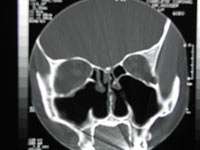

![]() CT scan of the nose after total bilateral turbinectomy | |

Turbinectomy is a procedure in which some or all of the turbinate bones in the nasal passage are removed, generally to relieve nasal obstruction.[1]